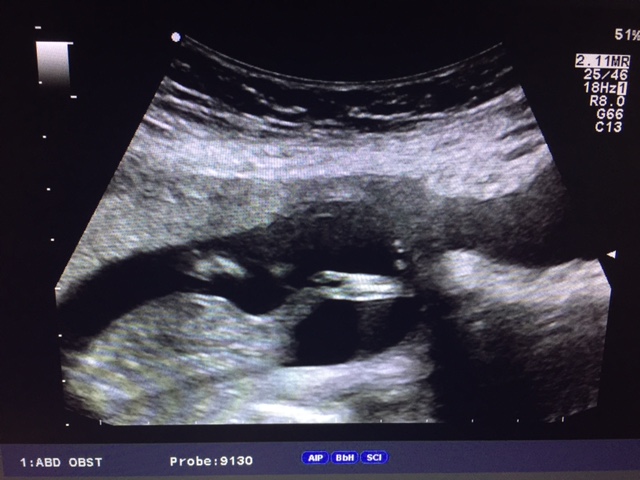

And our little babygirl

Attachment 28841